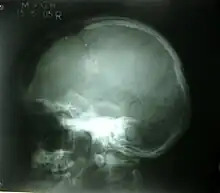

| A piece of a skull with a depressed skull fracture | |